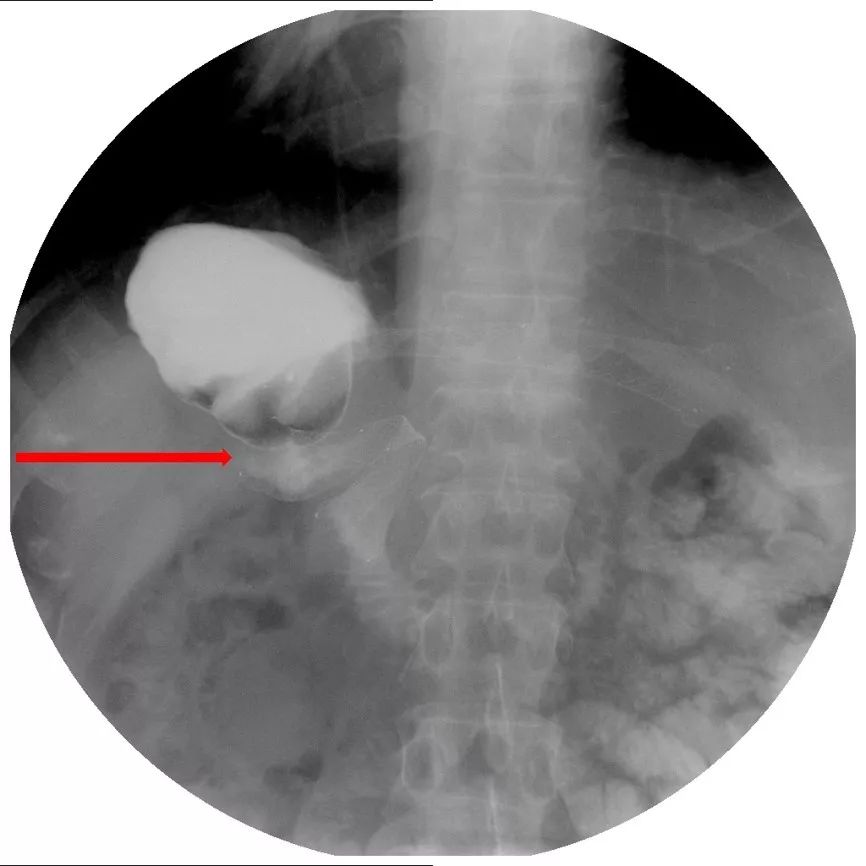

术后恢复可,行辅助化疗6周期,具体用药不详。2018年12月18日,患者口服卡培他滨化疗过程中出现恶心、呕吐,伴腹部疼痛,停止排气、排便。行胃镜示:胃大部术后,反流性食管炎,吻合口炎,胃潴留,慢性糜烂性胃炎。上消化道造影示:十二指肠水平部梗阻(图18)。

图18 上消化道造影见十二指肠水平部梗阻